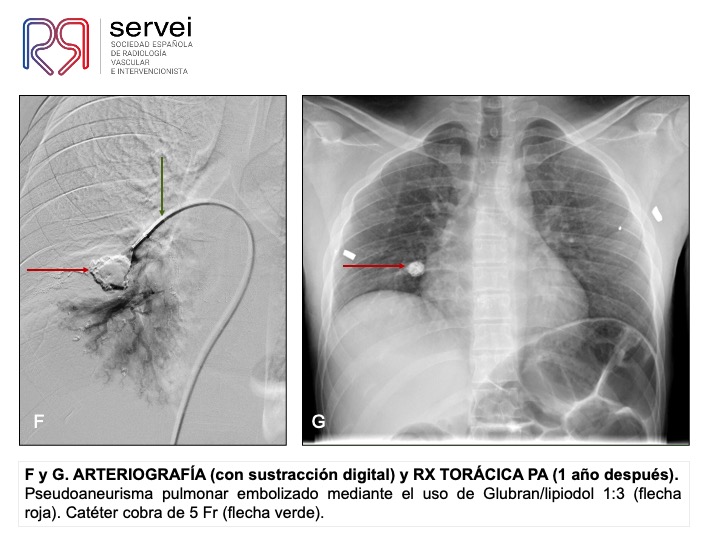

- Pseudoaneurisma pulnonar herida arma fuego 01

- Pseudoaneurisma pulnonar herida arma fuego 02

- Pseudoaneurisma pulnonar herida arma fuego 03

- Pseudoaneurisma pulnonar herida arma fuego 04

- Pseudoaneurisma pulnonar herida arma fuego 05

- Pseudoaneurisma pulnonar herida arma fuego 06

- Pseudoaneurisma pulnonar herida arma fuego 07

- Pseudoaneurisma pulnonar herida arma fuego 08

- Pseudoaneurisma pulnonar herida arma fuego 09

- Pseudoaneurisma pulnonar herida arma fuego 10

- Pseudoaneurisma pulnonar herida arma fuego 11

- Pseudoaneurisma pulnonar herida arma fuego 12